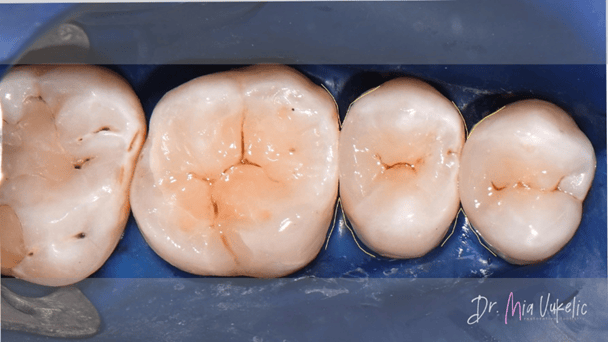

Después del proceso de pulido, la restauración fue recubierta con un sellador de superficie (sellador para resina PermaSeal™, Ultradent Products). Posteriormente, se realizó el control oclusal y radiográfico.

Como puede observarse en las imágenes finales, la resina Transcend™ ofrece una apariencia estética excepcional para la restauración. El sistema de matrices seccionales Halo permitió lograr una excelente anatomía proximal, tal como se aprecia en la radiografía.

Lograr una mimetización invisible en el sector posterior sigue siendo uno de los mayores retos en la odontología restauradora. En este caso, la combinación de la técnica centrípeta y las propiedades ópticas de Transcend facilitaron un acabado donde la línea de unión es imperceptible.